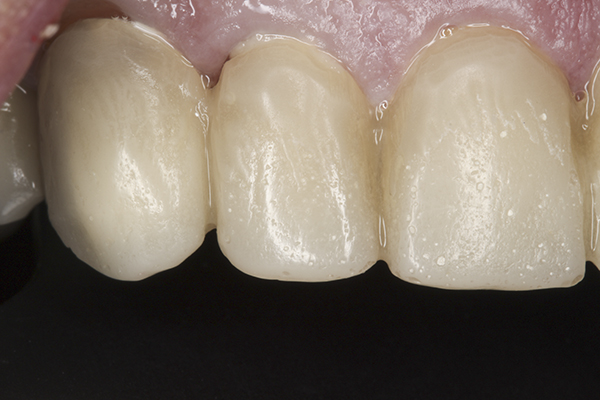

As the patient begins to function, canine guidance is created to eliminate any working side and most importantly, balancing side interferences during lateral excursive movements (Figure 2). Presence of interferences will further increase the possibility of hyperactive muscle activity and possible destruction of the teeth and joints.21 Anterior guidance is created to provide immediate separation of the posterior teeth during protrusive movements. When the posterior teeth are separated during functional movements, the amount of force delivered by the elevator muscles is significantly reduced. This natural programming allows for protection of the teeth along with relaxation and harmonious coordination of the muscles of mastication.22,23

(2.) Ideal occlusal design showing posterior occlusal contacts with anterior and canine guidance. guidance. Images adapted from content developed by The Dawson Academy.

Figure 2